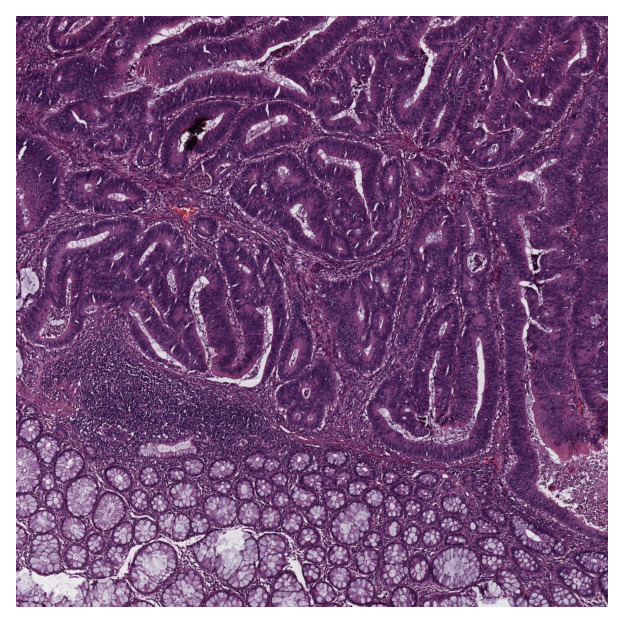

Get predictions for patches within an image tile¶

We now demonstrate how to obtain patch-level predictions for a large image tile. It is quite a common practice in computational pathology to divide a large image into several patches (often overlapping) and then aggregate the results to generate a prediction map for different regions of the large image. As we are making a prediction per patch again, there is no need to instantiate a new PatchPredictor class. However, we should tune the run input arguments to make them suitable for tile prediction. The run function then automatically extracts patches from the large image tile and predicts the label for each of them. The results will be saved in a specified location to avoid any problems with limited computer memory.

Now, we try this function on a sample image tile. For this example, we use a tile that was released with the Kather et al. 2016 paper. It has been already downloaded in the Download section of this notebook.

Let’s take a look.

../../_images/96fd7e685f13afddf92210d0ba9916c5947e2cfa0c00410dcd936a335a50da8c.png

|2026-01-09|12:38:32.168| [INFO] Tile size is: (5000, 5000, 3)